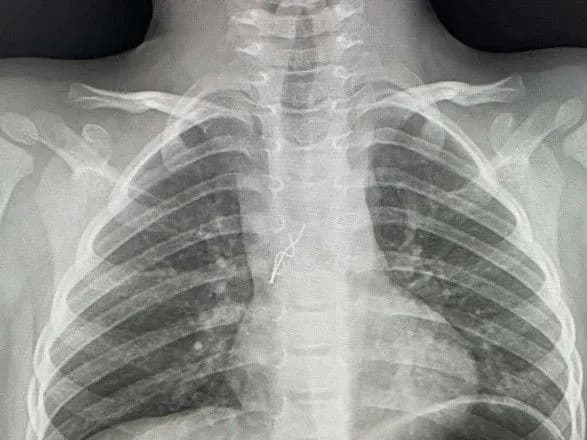

Лікарі зробили рентгтен і побачили стороннє тіло у дихальних шляхах. Діставали його з допомогою бронхоскопії, тобто без жодного розрізу.

"Гострими, направленими в різні сторони вусиками лампочка "дивилася" на мене. Вуса під час дихання травмували слизову оболонку в ділянці біфуркації трахеї, там уже утворилися дрібні крововиливи. Я захопив вусики щипцями і завів їх у тубус бронхоскопа, щоб під час видалення не травмувати ними бронхи і трахею. Разом з тубусом дістав лампочку з бронха дитини", — пояснив торакальний хірург Олександр Колодій.